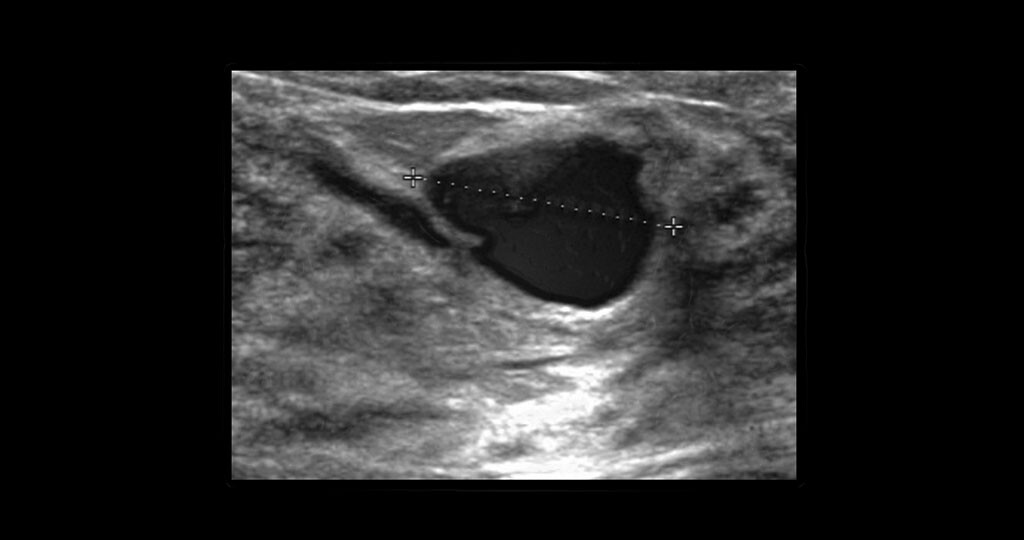

Ultraschall als Vorsorgeuntersuchung Die Ultraschalluntersuchung der Brust Mamma-Sonographie ist eine wichtige Untersuchungsmethode die ergänzend zu Tastuntersuchungen und dem Mammographie-Screening vor allem dem Entdecken von Brustkrebs dient. Neben der Mammographie also der Untersuchung der Brust mit Hilfe von Röntgenstrahlen hat sich die Mammasonographie die Untersuchung der Brust mit Ultraschall als zweites bildgebendes Verfahren etabliert.

Ultraschall-Diagnostik sollte Mammographie ergänzen Medizin 28052018 Kli Experten fordern dass die Brustuntersuchung per Ultraschall schon bei Routineuntersuchungen zur Früherkennung von Krebs standardmäßig zum Einsatz kommen sollte. Brust-Ultraschall Mammosonographie Eine Alternative zur Mammographie ist der Ultraschall der Brust auch Mammosonographie genannt. Jeder dritte Brustkrebs tritt bei einer Frau unter 50 Jahren auf.

Die radiologische Dichte der. Bei jungen Frauen Ultraschalluntersuchung sinnvoll Gerade bei jungen Frauen mit sehr dichtem Brustgewebe liefert die Mammografie eher unklare Ergebnisse. Ultraschall ergänzt Mammografie sinnvoll Junge Frauen werden deshalb nur in begründeten Ausnahmefällen zur Mammografie überwiesen da die Strahlenbelastung für sie problematischer sein kann.